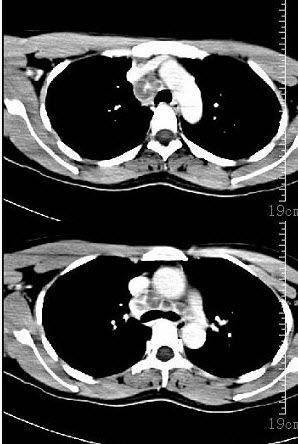

女,14岁,渐进性鼻塞2年余,右眼肿痛数月,CT如图所示,应诊断为()。

A:筛骨骨肉瘤

B:筛骨骨纤维瘤

C:筛骨软骨瘤

D:筛骨结核

E:筛骨骨化性纤维瘤